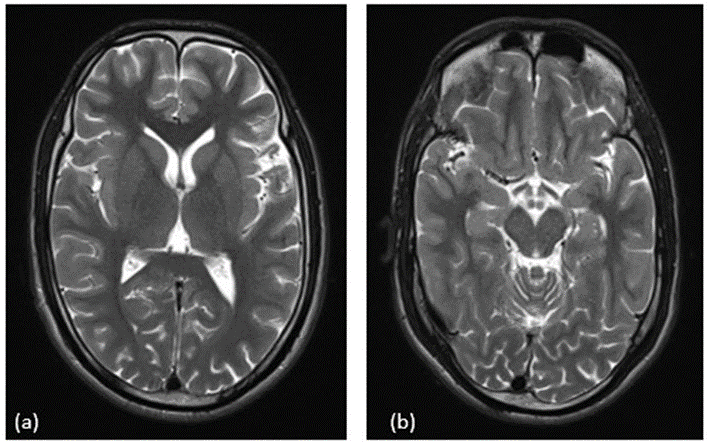

Figure 1. (a) T2-weighted MRI of the brain at basal ganglia level showing no abnormal signal intensity. (b) T2-weighted MRI at midbrain level also appears normal.

In light of the new cranial nerve findings and emerging behavioral symptoms, the possibility of Bickerstaff brainstem encephalitis (BBE) or Bickerstaff–GBS overlap was considered. Anti-GQ1b IgG antibody testing was planned. His electrolytes and metabolic parameters were within normal limits. EEG and MRI brain did not reveal any abnormality.

CSF analysis may reveal mild pleocytosis with normal protein levels. EEG and MRI are often normal and nondiagnostic, especially in paralytic forms as seen in our case [3,16,17]. RT-PCR of saliva and immunofluorescence staining of nuchal skin biopsies detect viral RNA and nucleoprotein antigen with sensitivities ranging from 50% to 100%, highest when serial samples are tested [5,19]. Postmortem detection of Negri bodies—eosinophilic cytoplasmic inclusions in infected neurons—remains a classic hallmark but may be absent early [4].